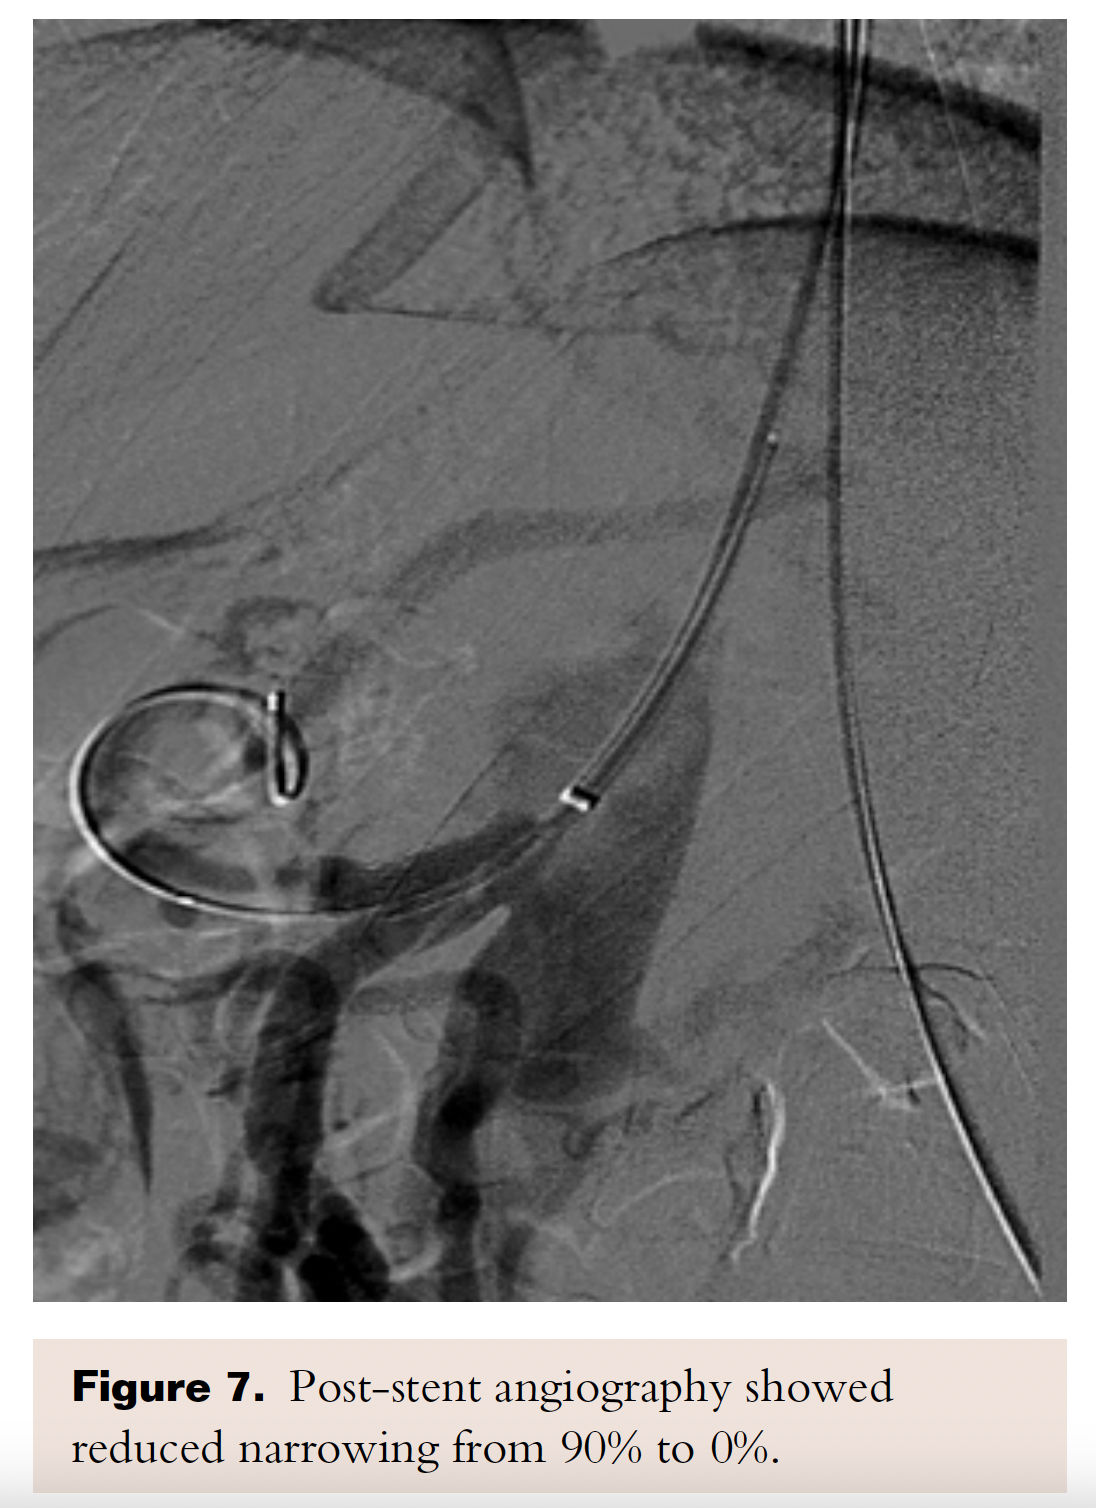

PTA of the proximal celiac trunk was performed with a 6.0 x 20 mm Mustang balloon. As expected, there was no significant angiographic improvement post balloon dilatation (Figure 6). A 6.0 x 16 mm Atrium stent was deployed across the target lesion at 12 atm. There was 0% stenosis post stent placement (Figure 7).